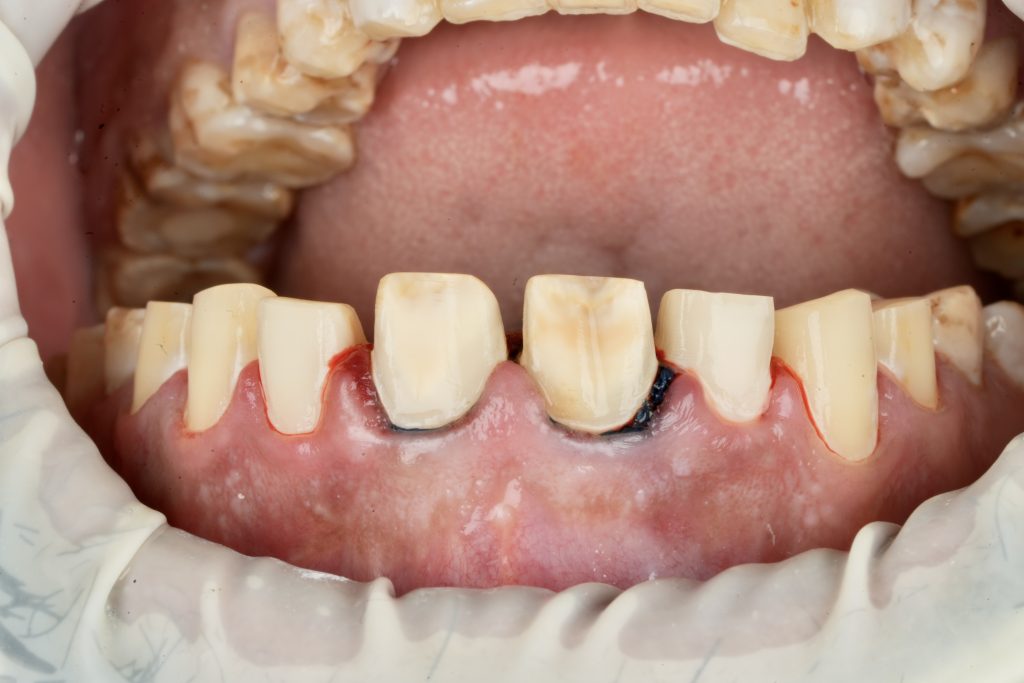

The patient sought esthetic improvement for uneven incisal edges, discolored anterior teeth, and disproportionate gingival display (Fig 1). A digital smile simulation and mock-up try-in were performed to assess tooth proportion, midline alignment, and incisal curvature. The plan prioritized enamel conservation and optical harmony.

2️⃣ Guided Tooth Reduction

Using silicone indexes derived from the mock-up, controlled minimal-thickness veneer preparations (0.3–0.5 mm) were carried out under microscope magnification to ensure uniform reduction and margin clarity (Fig 2). Finish lines were placed juxta-gingivally with soft-tissue protection using Teflon and double-cord isolation.